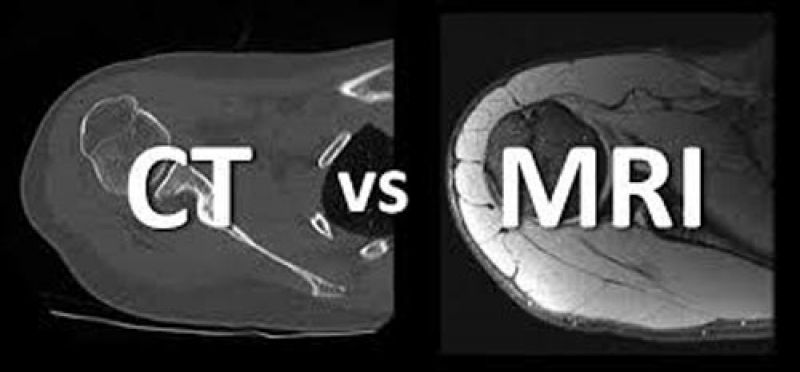

ਗੋਡਿਆਂ ਦੀ ਜਾਂਚ ਲਈ ਐਮ.ਆਰ.ਆਈ - ਗੋਡਿਆਂ ਦੀ ਐਮ.ਆਰ.ਆਈ ਦੁਆਰਾ ਗੋਡਿਆਂ ਦੇ ਵੱਖਰੇ ਭਾਗਾਂ ਦੀ ਜਾਂਚ ਕੀਤੀ ਜਾਂਦੀ ਹੈ ਅਤੇ ਬਿਮਾਰੀ ਦੇ ਕਾਰਨ ਦਾ ਪਤਾ ਲਗਾਇਆ ਜਾਂਦਾ ਹੈ। ਗੋਡਿਆਂ ਦੇ ਕਈ ਹਿੱਸੇ ਹੁੰਦੇ ਹਨ ਜਿਵੇਂ - ਹੱਡੀਆਂ, ਕਾਰਟੀਲੇਜ, ਟੇਂਡੰਸ, ਮਾਸਪੇਸ਼ੀਆਂ, ਲਿਗਾਮੇਂਟਸ ਅਤੇ ਖੂਨ ਦੀਆਂ ਕੋਸ਼ਿਕਾਵਾਂ ਆਦਿ। ਜਨਰਲ ਜਾਂਚ ਤੋਂ ਇਸ ਸਾਰੇ ਦੀ ਜਾਂਚ ਨਹੀਂ ਕੀਤੀ ਜਾ ਸਕਦੀ ਹੈ ਜਦੋਂ ਕਿ ਐਮ.ਆਰ.ਆਈ ਤਕਨੀਕ ਨਾਲ ਇਸ ਸਾਰੇ ਹਿੱਸਿਆਂ ਦੀ ਜਾਂਚ ਇਕੱਠੇ ਹੋ ਸਕਦੀ ਹੈ।

ਕਿਵੇਂ ਹੁੰਦੀ ਹੈ ਐਮ.ਆਰ.ਆਈ ਜਾਂਚ - ਐਮ.ਆਰ.ਆਈ ਨੂੰ ਮੈਗਨੇਟਿਕ ਰੇਜੋਨੇਂਸ ਇਮੇਜਿੰਗ ਕਹਿੰਦੇ ਹਨ ਮਤਲਬ ਇਸ ਤਕਨੀਕ ਵਿਚ ਮੈਗਨੇਟਿਕ ਰੇਜੋਨੇਂਸ ਦੇ ਦੁਆਰੇ ਸਰੀਰ ਦੇ ਅੰਗਾਂ ਦੀ ਅੰਦਰੂਨੀ ਹਾਲਤ ਦੀ ਜਾਂਚ ਕੀਤੀ ਜਾਂਦੀ ਹੈ। ਇਸ ਤਕਨੀਕ ਵਿਚ ਸ਼ਕਤੀਸ਼ਾਲੀ ਚੁੰਬਕੀ ਖੇਤਰ ਅਤੇ ਰੇਡੀਓ ਤਰੰਗਾਂ ਦੀ ਮਦਦ ਨਾਲ, ਸਰੀਰ ਦੇ ਅੰਦਰੂਨੀ ਅੰਗਾਂ ਦੀ ਛਵੀ ਕੱਢੀ ਜਾਂਦੀ ਹੈ।

ਇਸ ਤਕਨੀਕ ਵਿਚ ਮਸ਼ੀਨ ਤੋਂ ਇਕ ਕੰਪਿਊਟਰ ਜੁੜਿਆ ਹੁੰਦਾ ਹੈ, ਜੋ ਅੰਗ ਅਤੇ ਟਿਸ਼ੂ ਦੀ ਇਕ ਵਿਸ਼ਾਲ ਤਸਵੀਰ ਦਿਖਾਉਂਦਾ ਹੈ ਅਤੇ ਚਿਕਿਤਸਕ ਇਸ ਦੀ ਮਦਦ ਨਾਲ ਬਿਮਾਰੀ ਦਾ ਪਤਾ ਲਗਾਉਂਦੇ ਹਨ। ਇਸ ਤਕਨੀਕ ਨੂੰ ਮੈਗਨੇਟਿਕ ਰੇਜੋਨੇਂਸ ਇਮੇਜਿੰਗ ਕਿਹਾ ਜਾਂਦਾ ਹੈ ਕਿਉਂਕਿ ਇਸ ਜਾਂਚ ਦੇ ਦੌਰਾਨ ਜਾਂਚ ਵਾਲੇ ਅੰਗ ਨੂੰ ਬਹੁਤ ਪਾਵਰਫੁਲ ਮੈਗਨੇਟਿਕ ਰੇਜੋਨੇਂਸ ਵਾਲੇ ਏਰੀਆ ਵਿਚ ਰੱਖਿਆ ਜਾਂਦਾ ਹੈ।